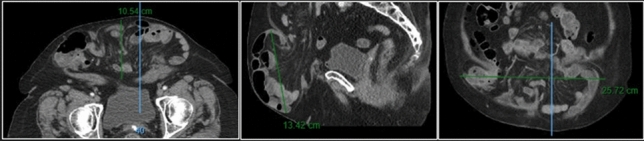

Methods and Procedures: Twenty-four patients underwent abdominal wall reconstruction (AWR) between January 2017 and June 2022 by a single surgeon at our institution. Lifestyle information (smoking, diabetes, and obesity status) and procedure-related metrics (pre-operative botox use, hernia characteristics, and mesh type) were obtained. The ellipsoid formula (V = 4/3ABC) was used to calculate volume of the hernia sac (VIH) and abdominal cavity (VAC) (Fig. 1). Measurements at initial visit and time of surgery were compared and analyzed using a two-tailed T Test (p < 0.05 signified significance).

Fig. 1 Hernia sac measurements for calculating VIH (Left to right: axial, sagittal, coronal)